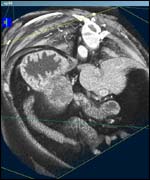

| Tuesday, 1 October, 2002, 10:16 GMT 11:16 UK 3D images transform cancer surgery ![]() Surgeons can watch the image while feeling the tumour Surgeons in Manchester are using 3D graphics to transform operations on cancer patients. Doctors at Manchester Royal Infirmary use the latest computer technology to take 3D images of cancer tumours. That image is then beamed onto a wall in the operating theatre to guide the surgeon during the procedure.

"We work with cancers in the liver or pancreas," says Mr Rory McCloy, a consultant surgeon at the hospital. "These tumours are deep inside the abdomen. It is major surgery to get these cancers out. If you cut across the tumour you can spread the cancer around the body. "By looking at the scan on the wall, we can almost practise before we start to try to remove it. "We can move the image around while at the same time holding the tumour inside the patient's body." Early stages Mr McCloy first used the technology during an operation on one patient in April. He is now planning to use it more widely over the coming months.